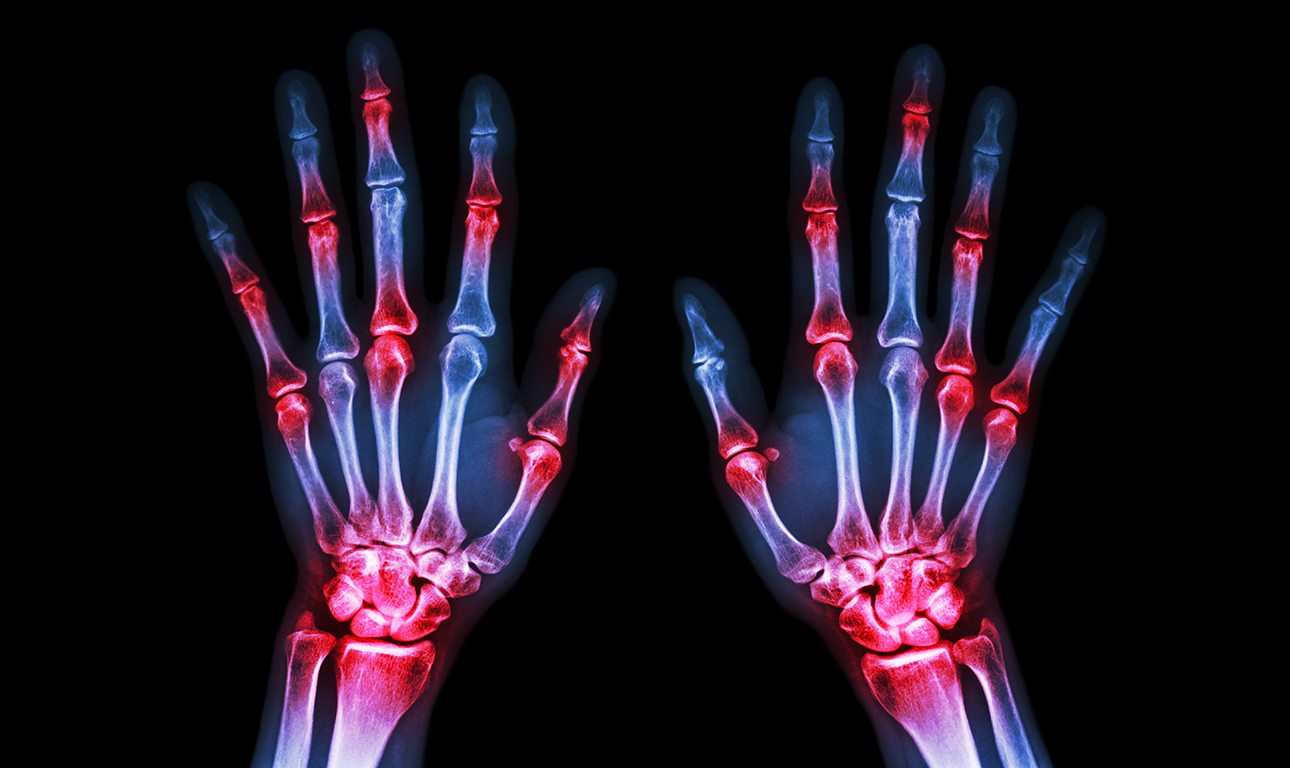

Σε αντίθεση με τις κοινές μορφές της αρθρίτιδας, που εκδηλώνονται όταν φθείρονται οι χόνδροι στις αρθρώσεις λόγω της προόδου της ηλικίας, η ρευματοειδής αρθρίτιδα αναπτύσσεται όταν το ανοσοποιητικό σύστημα επιτίθεται και προσβάλει τις αρθρώσεις, προκαλώντας πόνο και πρήξιμο.

Η ρευματοειδής αρθρίτιδα μπορεί να προκαλέσει μόνιμη βλάβη και παραμόρφωση στις αρθρώσεις, ειδικά στα αρχικά στάδια της νόσου. Για τον λόγο αυτό, είναι σημαντική η έγκαιρη διάγνωσή της και γίνονται οι προσπάθειες ανακάλυψης νέων μεθόδων.